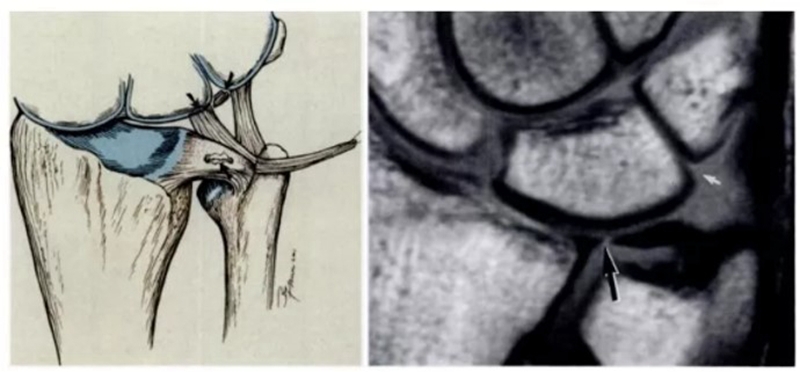

(2)MRI

ⅠA,TFCC中心穿孔,A、B三角软骨盘正常弓形低信号缺损;C轴位显示三角软骨盘中心的高信号区与D关节镜一致

ⅠB,TFCC尺侧撕裂;TFC尺侧附着处信号增高

ⅠC,尺三角韧带撕裂

ⅠD,TFC桡侧撕裂,桡侧附着处及桡尺关节处信号增高